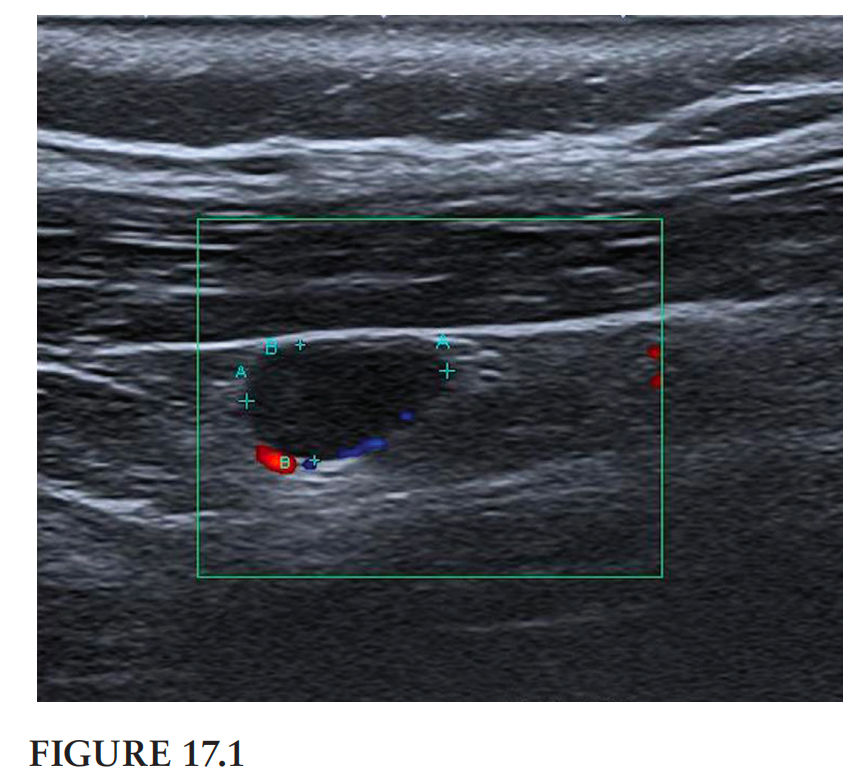

翻译:祁海丽;校对:石慧17 This ultrasound image (Figure 17.1) shows the midcervical region...

兽医英语学习中心翻译:祁海丽;校对:石慧17 This ultrasound image (Figure 17.1) shows the midcervical region...